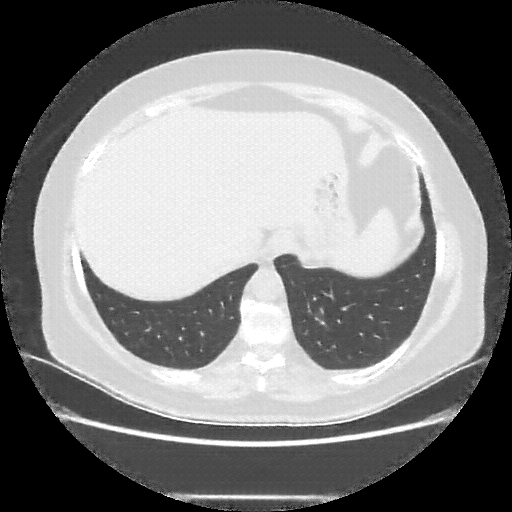

Original NATIVE CT scan (input)

No window - Raw intensity values

Lung window (WL -600, WW 1500 β†’ Low βˆ’1350, High +150)

Mediastinum window (WL 40, WW 400 β†’ Low βˆ’160, High +240)